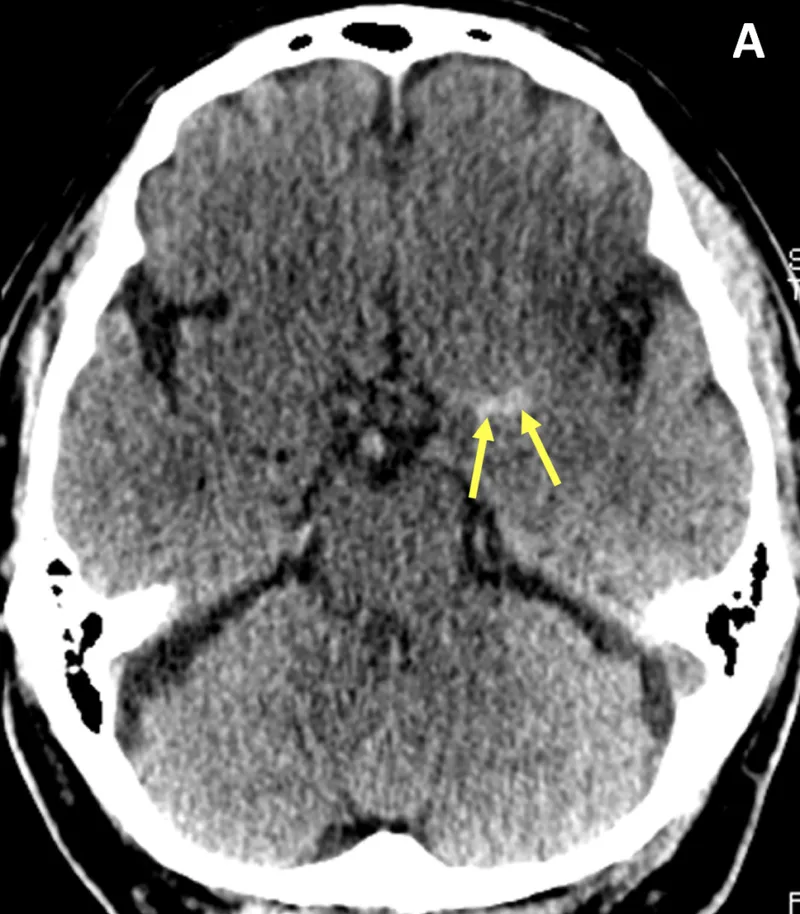

Stroke imaging :

| CT head non-contrast | All suspected strokes within 1h | Haemorrhage 95%, early ischaemia 60% |